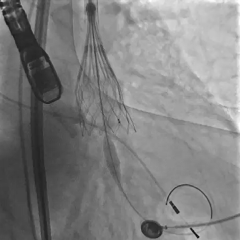

根部造影,可见大量反流

第一次展开,瓣膜形态敞口

第二次展开,瓣膜位于0位;此时患者发生室颤,除颤后进行按压

瓣膜按压后位置发生变化

多体位观察

瓣膜位于瓣上,选择回收

再次定位释放